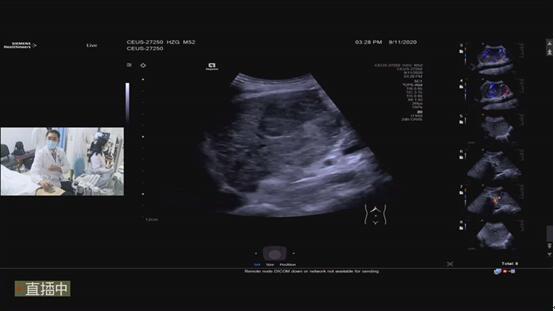

周建华主任结合科室典型病例对最新国际权威指南进行了深入浅出讲解。裴小青主任医师、刘隆忠副主任医师、邹如海副主任医师和郑玮主治医师结合科室经验和前沿研究成果,分别对超声造影在肿瘤疗效评估、肝转移瘤术中诊断及穿刺活检等进行了详细讲授。韩峰副主任医师规范化演示了超声造影操作和诊断思路。郭智兴、王建伟、韩竞和李擎四位主治医师通过几个精彩病例演示展示了复杂病例的诊断思路。周建华主任和裴小青主任医师分别对病例进行了精彩的点评。